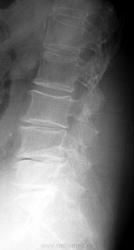

Вот такой пример.....Женщина 72 лет. Жалобы на резкие боли при малейшем движении. Передвигается с трудом.

Как поступить тут? Только описать изменения? Дать собственные выводы?

А снижение высоты диска L5-S1 с наличием соответствующих изменений позвонков и даже вакуум-феномена?...ведь это из другой оперы...